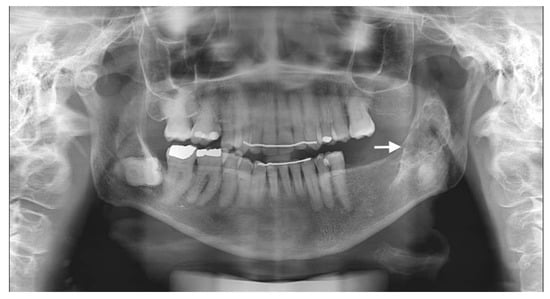

The usual diagnostic imaging study with a panoramic radiograph showed a well-defined mixed radiolucent–radiopaque lesion with peripheral enhancement in the left mandibular ramus occupying almost its entire thickness (Figure 1). Computed tomography performed with contrast was used to confirm the existence of a heterogeneously enhancing 3 cm long tumor with lobulated margins and bicortical expansion without bone perforation. Radiographically, there appeared to be an expansile cystic mass with areas of calcification and sclerotic borders. The mandibular lower border was intact (Figure 2A,B).

Figure 1. Preoperative panoramic radiographic image. Radiolucency with many radiopaque spots described as driven snow appearance. No association with impacted teeth was seen (see arrow).